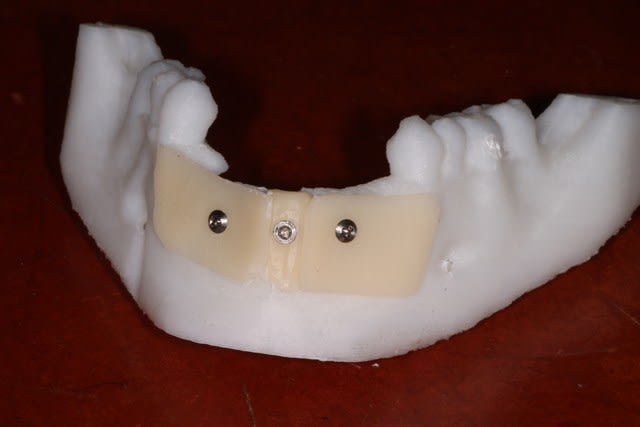

Voici 3 possibilités traité sur la maquette mandibulaire.

2 blocs biobank 20x10 :700 € + membrane et vis

Coffrage avec prélèvement ramique : biomateriaux + vis , de la membrane et de la sueur .

Coffrage avec membrane en PDLLA 126x11x0,8mm :300 € ttc + biomatériaux ( autogene + minéros, c'est pas mal ) + vis d'espacement et de fixation + membrane collagene ( http://www.biagginimedical.com/#!sonicweldrx/civk )

L'étude me fait éliminer le coffrage ramique, car je me retrouve avec une assez faible épaisseur au niveau de 32 42, ( sans parler de la difficulté du prélèvement, vu le peu d'os disponible ).

Reste les blocs, et un coffrage en adaptant la technique sonicweldrx en fixant la membrane PDLLA avec des vis d'ostéosynthèse.

j'avais cru voir dans un kit de vis, des vis d'espacement avec une minivis dans la tête, pour fixer la membrane , mais je ne sais pas si j'ai rêvé, je ne retrouve pas le site web correspondant ( voir mon schéma )

Bravo pour les maquettes, très beau travail de réflexion!

Je pour la forme, faut 2 vis par bloc, sinon ça bouge...